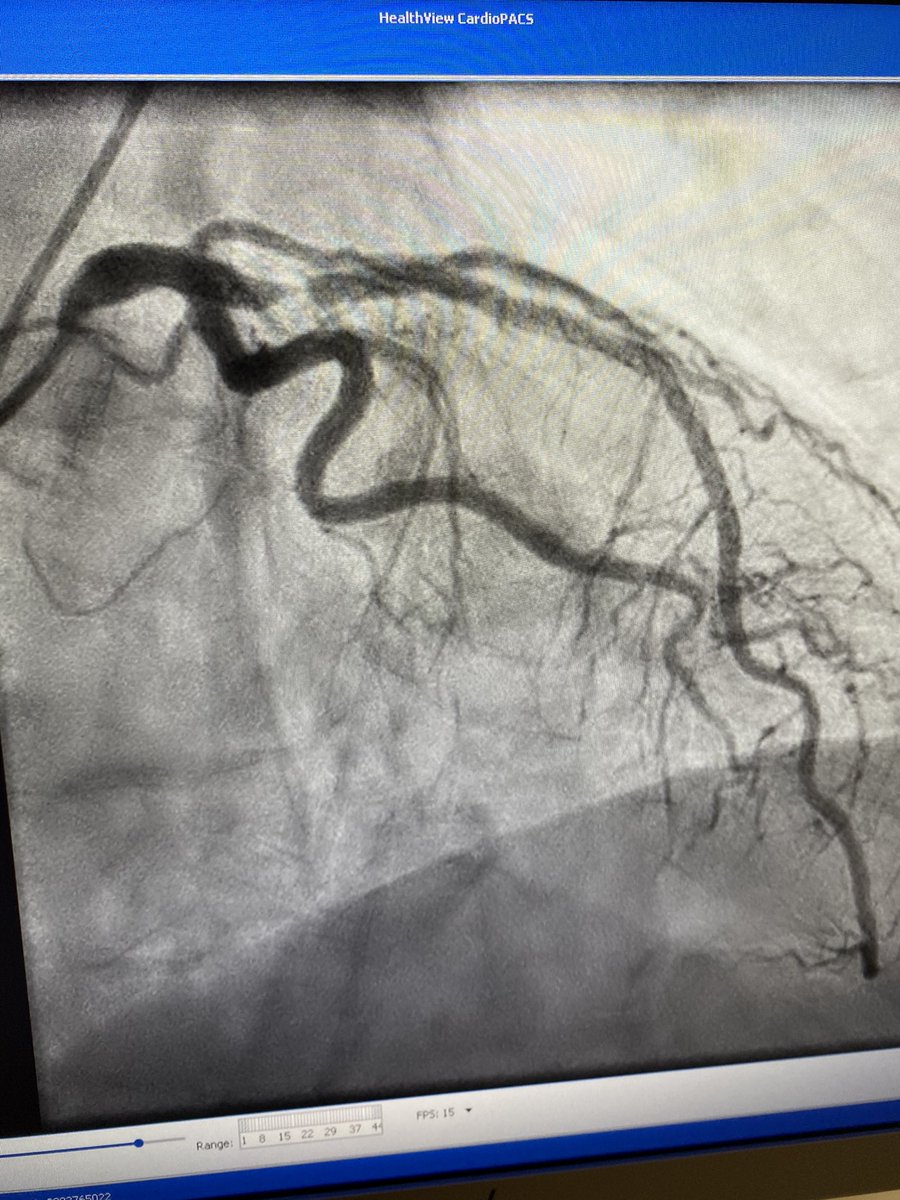

IVUS must be incorporated into you practice. 72 m with Recent LAD stent. Severe new denovo lesion at Prox stent edge. Stent placed 9 months prior.

Dropped new stent 4.5mm and postdilated old stent to 4.25mm. Post IVUS with excellent expansion and no more malapposition. Looks grossly oversized on post angio.